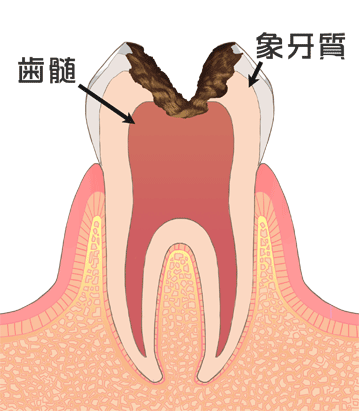

歯根破折を起こしてしまう歯のほとんどが、過去に虫歯で神経を抜かれた歯です、

歯が痛くて、歯の神経を抜くと、痛みは無くなるのですが、いつか歯根破折を起こすリスクを背負うことになります。

歯根破折を防ぐには、歯の神経を抜くような虫歯を作らないことが一番の予防策です。